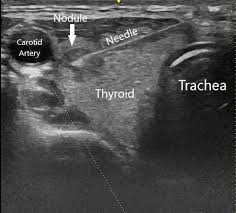

Ultrasonography Of The Thyroid Endotext Ncbi Bookshelf from www.ncbi.nlm.nih.gov A thyroid nodule can feel like a bump on the side or in the middle of the throat. Ultrasound is used to see the thyroid gland and the lymph node of the neck. Throat cancer is a condition that is characterized by the development of malignant tumors in the throat (pharynx), voice box (larynx) or tonsils. The cells are then looked at closely in the lab. In fact, the risk of cancer in any individual with thyroid nodules is. Some different types of cancers that can be detected. Throat cancer refers cancer that develops in your throat (pharynx) or voice box (larynx). Two in three cases of thyroid cancer occur in people under age 55, and 75%.

Ultrasound is often one of the first line tests in the detection of cancer. Keep in mind, however, that an ultrasound alone cannot make the diagnosis of cancer. Ultrasounds can produce false positives. Thyroid nodules are lumps that can appear in the thyroid gland in front of the throat. They increase with age and, in fact, if you look with sensitive measures like ultrasound, over 50% of people will have thyroid nodules by the age of 50 or 60. This test will usually help determine that the nodule has a low chance of being cancerous (has characteristics of a benign nodule), or that it has some characteristics of a cancerous nodule, and therefore a biopsy is indicated. Ultrasounds are not useful for treatment monitoring. While it can't diagnose cancer, it can detect the abnormal tissues that may possibly be cancerous. A small transducer (probe) both transmits sound waves into the body and records the waves that echo back. My 3.8 year old's neck ultrasound shows chain of lymph nodes bilaterally with largest on right 14mm by 6mm and largest on left 13mm by 6mm,the left one is there since a year.few intraparotid largest 5mm.thyroid & both submandibular normal. Staging head and neck cancers The most common symptom of thyroid cancer is a hard lump on the neck—but most patients experience no symptoms at all. Doctors often use them to guide a needle during a biopsy.